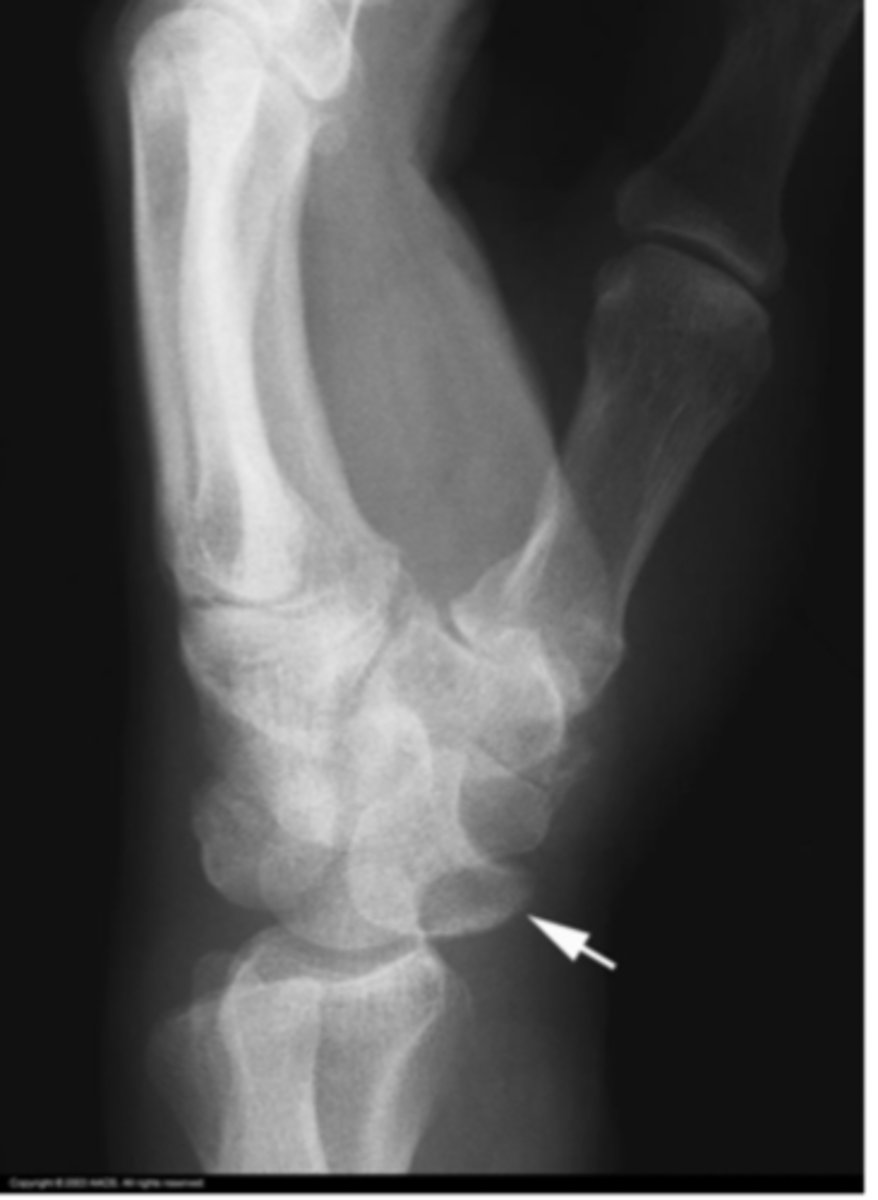

Lunate instability

What is the issue?